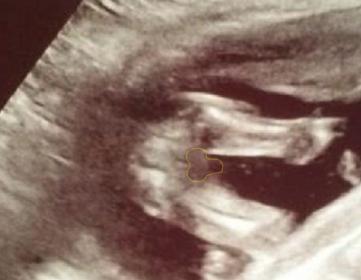

17+5 Potty Shot, Girl or Boy???

This ultrasound was only 1 minute long (seriously!). My phone had died, too. ANYWAYS, this is the only picture I got. Babe had legs closer together in the first 30 secs and while she was measuring, which I told her no I want to know gender. Which she didnt even say, just printed this picture...So frustrating. I was also telling her if its a girl I want you to point out the labia. lol

My anatomy scan is May 13th at the American hospital in Seoul. I am going to try to wait... Until then, could anyone tell boy or girl?

These are the same picutres just different lighting.